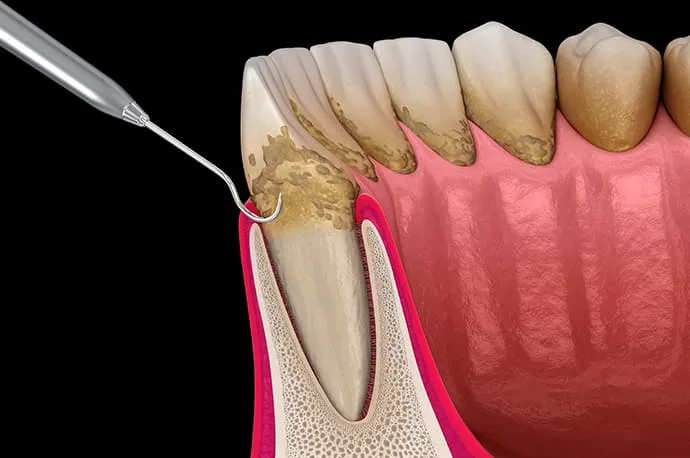

歯周病とは、「歯の周りの病気」という言葉の通り、歯を支えている歯ぐきや骨が、細菌によって少しずつ壊されていく病気です。歯の表面に細菌のかたまり(プラーク)が付着すると、その周囲で炎症が起こり、歯ぐきの腫れや出血がみられるようになります。さらに進行すると、歯を支える骨が溶かされ、歯がぐらつく原因にもなります。

歯周基本治療では、歯ぐきの隙間から器具を入れ、歯ぐきの下に付着した歯石を除去します。この際、手の感覚を頼りに処置を行うため、平たい歯石や器具が入りにくい部位では、歯石が取り残されてしまうことがあります。

歯石の取り残しがある場合や、歯周組織の改善が十分に認められない場合には、歯ぐきを切開して開き、歯石を直接目で確認しながら除去します。